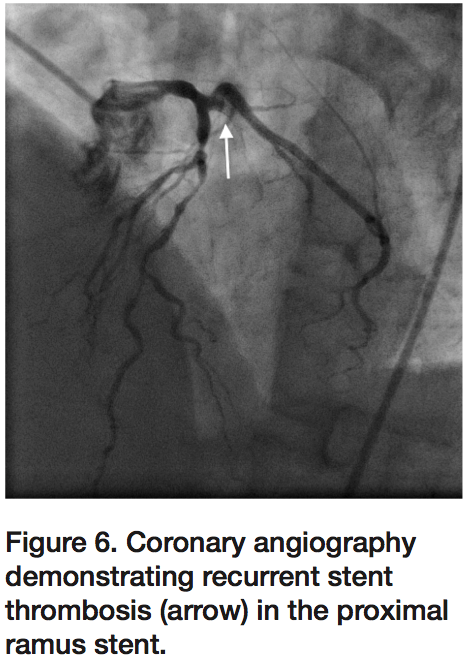

mitral regurgitation. Percutaneous coronary intervention (PCI) was performed in the same setting after anticoagulation using bivalirudin bolus and infusion, and antiplatelet therapy using aspirin 325 mg and clopidogrel 600 mg pre-procedure. The RI lesion was treated with a 2.25 x 24 mm Ion stent (Boston Scientific) and post-dilated using a 2.5 mm non-compliant balloon. Final angiography demonstrated TIMI-3 flow in the RI (Figure 2), and the patient was transferred to recovery in stable condition.

As the patient was being transferred off the procedure table, he once again developed severe chest pressure and recurrent lateral ST elevations. Angiography again demonstrated 100% thrombotic occlusion of the RI at the proximal edge of the previously placed stent (Figure 6), despite a repeat ACT of 337 seconds. Intravenous eptifibatide was initiated in addition to bivalirudin infusion. Aspiration thrombectomy was performed with multiple passes using an Export catheter followed by IVUS, which again confirmed adequate stent